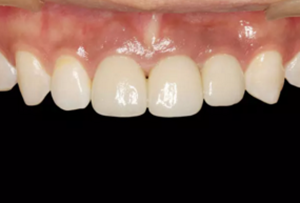

圖23 最終修復(fù)后即刻口內(nèi)像

圖25 最終修復(fù)后復(fù)查口內(nèi)像